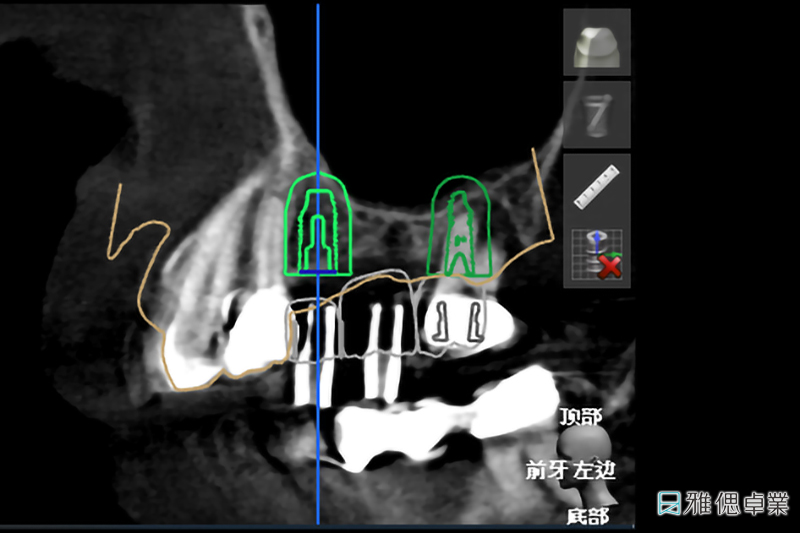

數位植牙是藉由影像導引(Imaging Guide)的技術保留手術導引(Surgical Guide)與電腦導航(Navigation)技術的優點,讓牙醫師在進行植牙手術時,清楚知道鑽孔的軸向與位置,即時改變或修正植牙手術計劃。

在植牙療程的過程中,專業醫師會透過「植牙規劃軟體」找出合適的植體大小及植入位置、角度與深度,再為患者設計專屬「手術引導板」,將手術引導板安裝在於患者的缺牙位置,定位適當的角度、位置與深度,快速完成高效能數位植牙療程、大幅提升植牙治療的舒適體驗!

植牙手術導引板設計過程